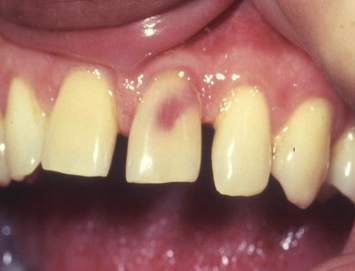

internal resorption affecting crown

pink tooth of mummery